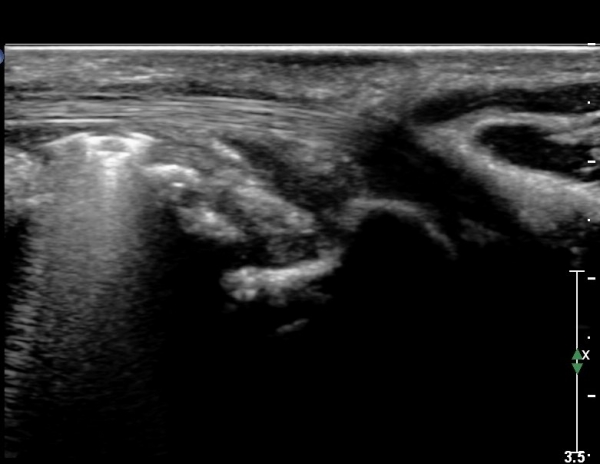

¾Æ·§ÆÈ ÇϺκΠȾ´Ü¸é°Ë»ç¿¡¼­ Àü°ñ°£ ½Å°æ Áö¹è¸¦ ¹Þ´Â  PQ ¿¡¼­ ½Å°æ¸¶ºñ ¼Ò°ß(°í¿¡ÄÚ ±ÙÀ§Ãà)À»

º¸ÀÌÁö ¾ÊÀ¸³ª  FPL ÈûÁÙÀÇ Àú¿¡ÄÚ ºÎÁ¾ÀÌ °üÂûµÇ°í(»çÁø 2, 3) ³»°íÁ¤¹°ÀÌ FPL °ú Á¢ÃËÇϰí ÀÖÀ½ÀÌ °üÂûµÊ(»çÁø 3)